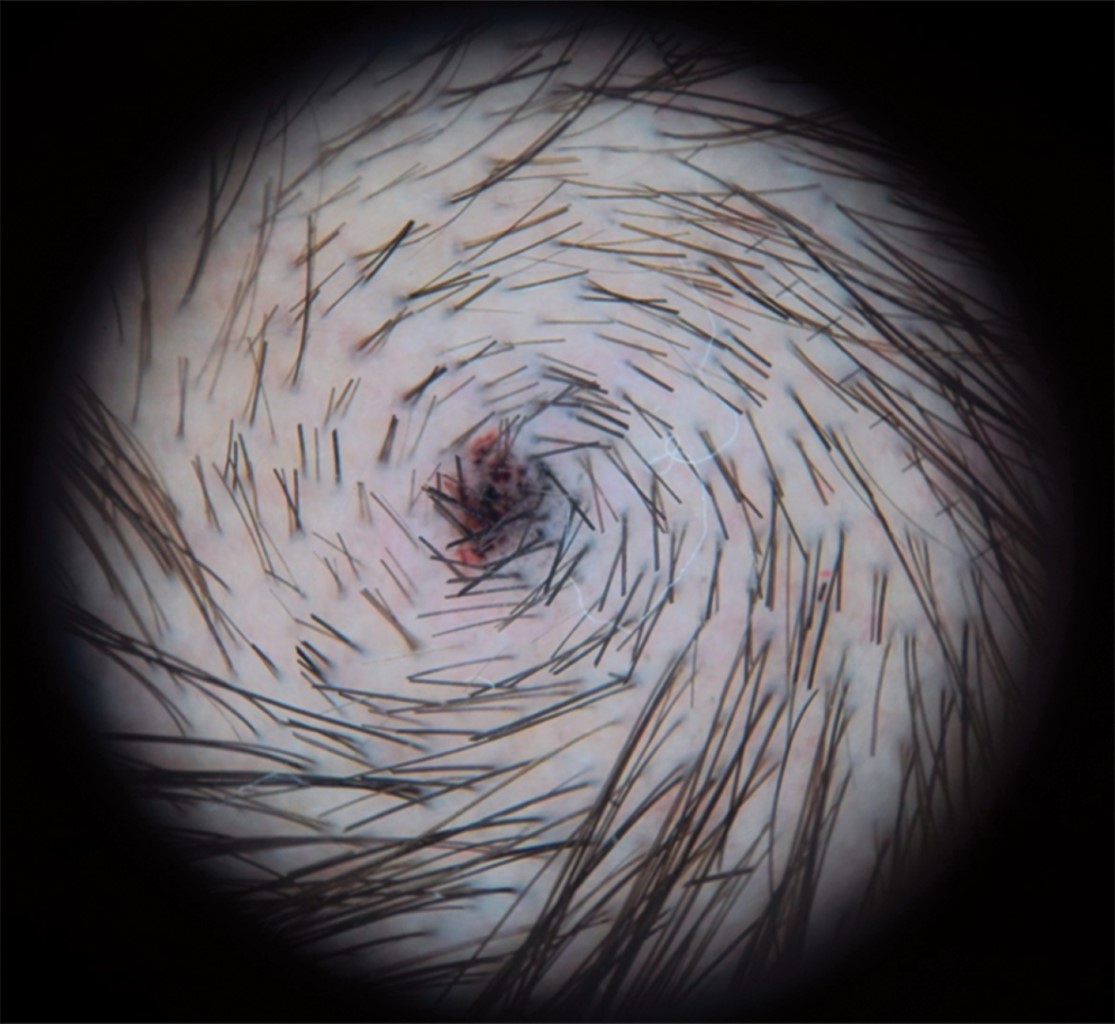

En cada sesión se realizó iconografía clínica y dermatoscópica (a todos los pacientes se les realizó en la consulta basal un tatuaje puntiforme en el vértex para asegurar que se evaluara siempre la misma área) (Figura 2), así como aplicación de los cuestionarios DLQI, de satisfacción y de registro de eventos adversos con una escala de intensidad visual. La iconografía clínica fue evaluada por tres dermatólogos ciegos a la asignación y en la iconografía dermatoscópica se realizó el conteo de pelos/cm2 por un dermatólogo ciego al estudio.

Figura 2